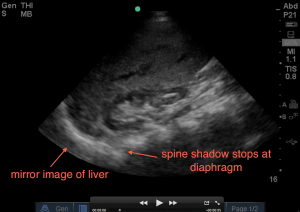

1. Evaluate above the diaphragm…. to evaluate for intrathoracic free fluid. This may involve having to increase your depth while you slowly fan your probe anterior to posterior. The patient’s breathing will also help you as you will notice the bright white (echogenic) linear diaphragm which hugs the liver will move (right and left) on your screen with every breath. Having the patient take a deep breath and holding it, will allow you better visualization if a rib shadow is in your way. A mirror image of the liver should be seen above the diaphragm (a normal artifact that occurs when ultrasound passes through structures of varying densities and then through air (lung). If no mirror image, and the area above the diaphragm is anechoic (black) – that’s fluid in the thoracic cavity! The spine sign will also help you evaluate for free intra-thoracic fluid, as the spine and it’s shadowing normally stops once it hits the diaphragm when visualizing on the screen from right to left (air is the enemy of ultrasound!). But if there is fluid in the thoracic cavity, you will see the spine continue to traverse past the diaphragm up into the thoracic area (fluid is the lover of ultrasound!).